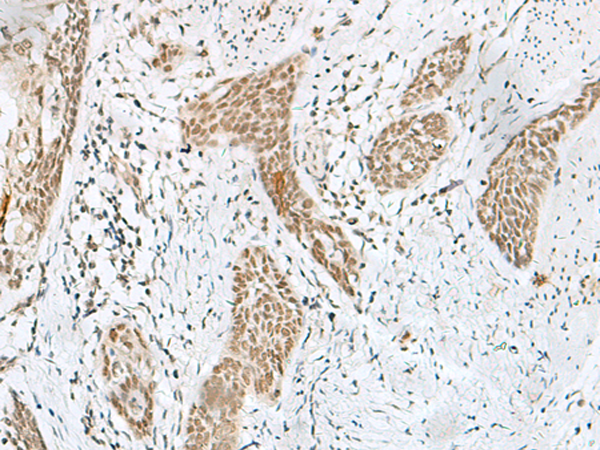

IHC positive control:

Human esophagus cancer